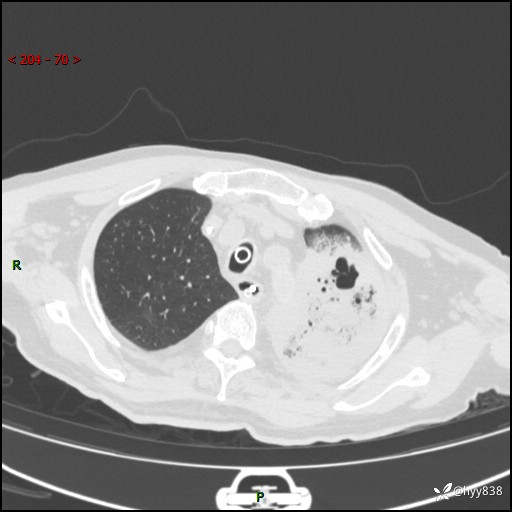

胸部CT平扫(2024.7.24)